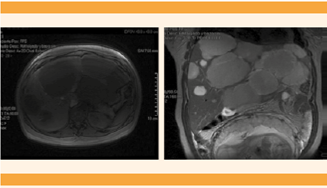

Los estudios se complementaron con resonancia magnética para determinar el tamaño de las lesiones, el hallazgo de múltiples lesiones nodulares de diferente tamaño y distribución difusa, bordes debidamente delimitados, irregulares y microlobulados. Se concluyó que se trataba de un caso de hepatomegalia asociada con múltiples lesiones que sugerían hemangiomas gigantes.Figura 2

Figura 2 Hepatomegalia asociada con múltiples lesiones nodulares de diferente tamaño y distribución difusa, bordes bien delimitados, irregulares y microlobulados. Segmento IV: 15 x 10 x 10 cm con una cicatriz central hipertensa en T2 e hipotensa en T1.